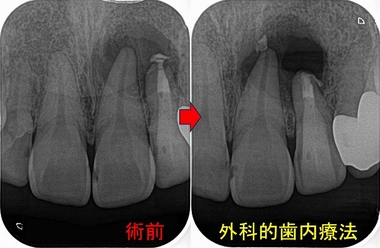

レントゲン

かなり大きな根尖病変が見られます。

また以前の根管治療で相当根管を削ったようでこの状態だと最後の処置として外科的歯内療法

で保存治療を行うか!?

根尖病変は左上1にもかかっていますが、電気歯髄診査では左上1は生活反応があり神経は問題無いと考えました。

外科的歯内療法

かなり大きな病変で真っ黒な黒い部分は唇側から口蓋側までトンネル状に骨が全くありませんでした。